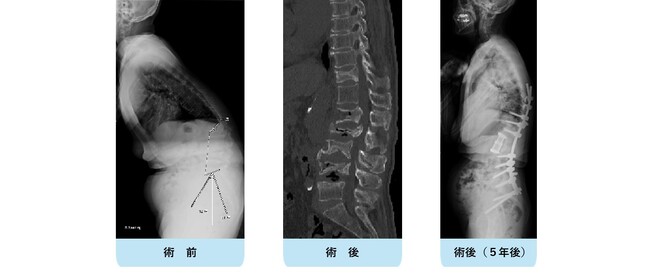

当院では近年増加傾向の成人脊柱変形矯正手術も積極的に行っています。以前は成人・お年寄りの腰曲がり・脊柱変形に対する適切な手術方法がなく、そのような患者さんで日々困っているような方がいらしても対症療法を行うことしかできませんでした。しかし昨今、成人・お年寄りの腰曲がり・脊柱変形は手術に耐えられる体力と治療意欲があれば多くが治せる時代になりました。腰仙椎を固定することにより体の柔軟性が失われ、日常生活動作に多少影響が出てくるものの、大幅な疼痛の改善、体幹バランスの安定、歩行能力の向上など得られるメリットはとても大きいです。腰が曲がって辛いのを「年だから」と治療を諦めてしまっている患者さんが多いですが、まず腰曲がりによる難治性疼痛を病気と認識して頂くことが大事です。つまり病気であれば、治療できる可能性があるので是非一度お気軽にご相談下さい。毎週火曜日と木曜日に側弯・脊柱変形外来を開設しています。紹介状なしでの受診も可能ですので、ご利用下さい。(側弯・脊柱変形外来はこちら)

変性後側弯症で正面・側面ともに体幹バランスが破綻しています。まず腰椎側方進入前方固定術を行い、ある程度の矯正、土台を形成。1週間後に胸腰仙椎後方矯正固定術を行いました。正面・側面ともにバランスが良好に維持され、難治性の腰痛が改善しました。

典型的な変性後側弯症、成人脊柱変形の症例です。正面、側面いずれもバランスが破綻していて、立位持続・歩行が困難な状態です。

腰椎側方経路椎体間固定術と後方矯正固定術を2回に分けて行い、正面・側面ともに生理的なshapeが獲得されています。重要なことは、近年この生理的なshapeを取り戻すことが腰痛・歩行障害など患者さんの愁訴の改善に直結することが分かっていることです。